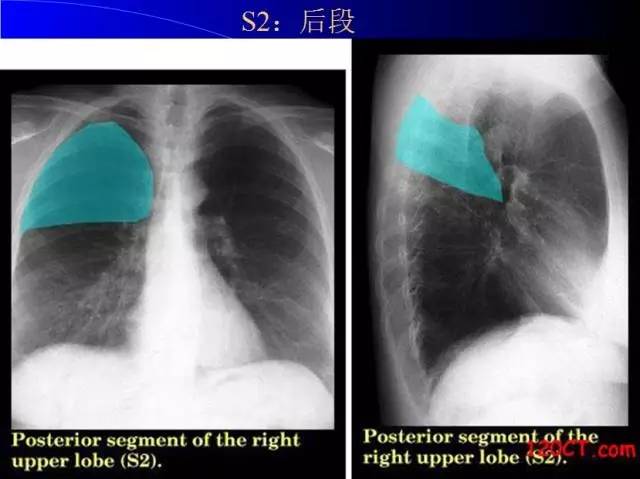

肺部基础X片及CT片解读